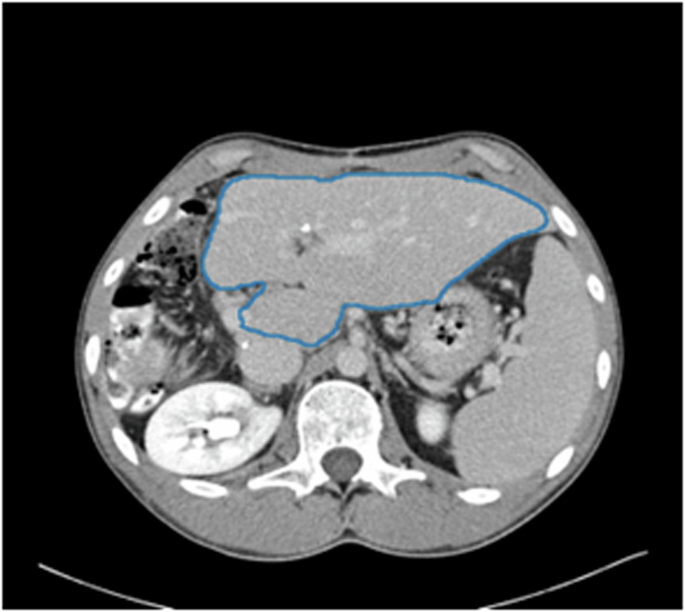

The field of radiology, which relies on the expert interpretation of medical images like CT scans and MRIs, provides a perfect case study for the transformative power of multimodal AI. Recent breakthroughs in this area are a major focus of GPT in Healthcare News, demonstrating a tangible leap beyond traditional computer vision metrics.

For years, AI in radiology has focused on narrow tasks using standard computer vision models. These models might be excellent at one specific thing, like detecting a nodule in a lung CT scan (segmentation) or classifying an image as “abnormal” (classification). However, they lack clinical context. They cannot read the patient’s history, understand the radiologist’s preliminary notes, or generate a nuanced, human-readable report that synthesizes all available information. Furthermore, evaluating these AI-generated findings has relied on pixel-based metrics (like Intersection over Union) or text-based metrics (like BLEU score for report generation), which often fail to capture clinical significance. A model could be 99% accurate at the pixel level but miss the one tiny, clinically crucial detail a human expert would spot.

How GPT-4 Vision Revolutionizes Radiological Evaluation

A multimodal approach, powered by models like GPT-4, changes the game entirely. Imagine a system that is given a series of CT scan images along with the patient’s electronic health record, which includes symptoms, lab results, and previous diagnoses. The model can:

- Visually Identify Anomalies: It analyzes the CT images to identify potential findings, such as lesions, fractures, or inflammation.

- Correlate with Clinical Text: It cross-references these visual findings with the patient’s history. For example, it might note that a newly identified lung nodule is particularly concerning given the patient’s history as a long-term smoker.

- Generate Clinically Aligned Reports: Instead of just outputting coordinates of a finding, it can generate a comprehensive, coherent paragraph for a radiology report, using standard medical terminology and highlighting the most critical findings in order of clinical importance.

Data, Performance, and the Future of Diagnostics

Early results from such systems are incredibly promising. In controlled studies, these multimodal evaluation frameworks have shown a much higher correlation with the consensus of human radiologists than traditional automated metrics. This is because the model understands *why* a finding is important, not just *where* it is. This represents a significant development in GPT Fine-Tuning News, as these models are not just pre-trained but are custom-tailored for highly specific, high-stakes domains. The datasets required for this are complex, pairing high-resolution medical images with detailed, anonymized clinical data, a key topic in GPT Datasets News.